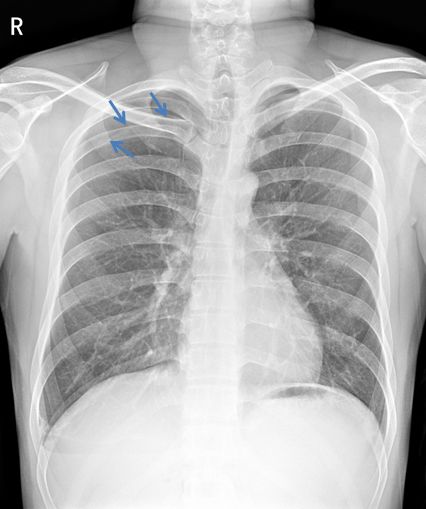

病例4患者的X线胸片

患者右肺上叶可见肺叶压缩带边缘,肺叶压缩约5% (蓝色箭头)。